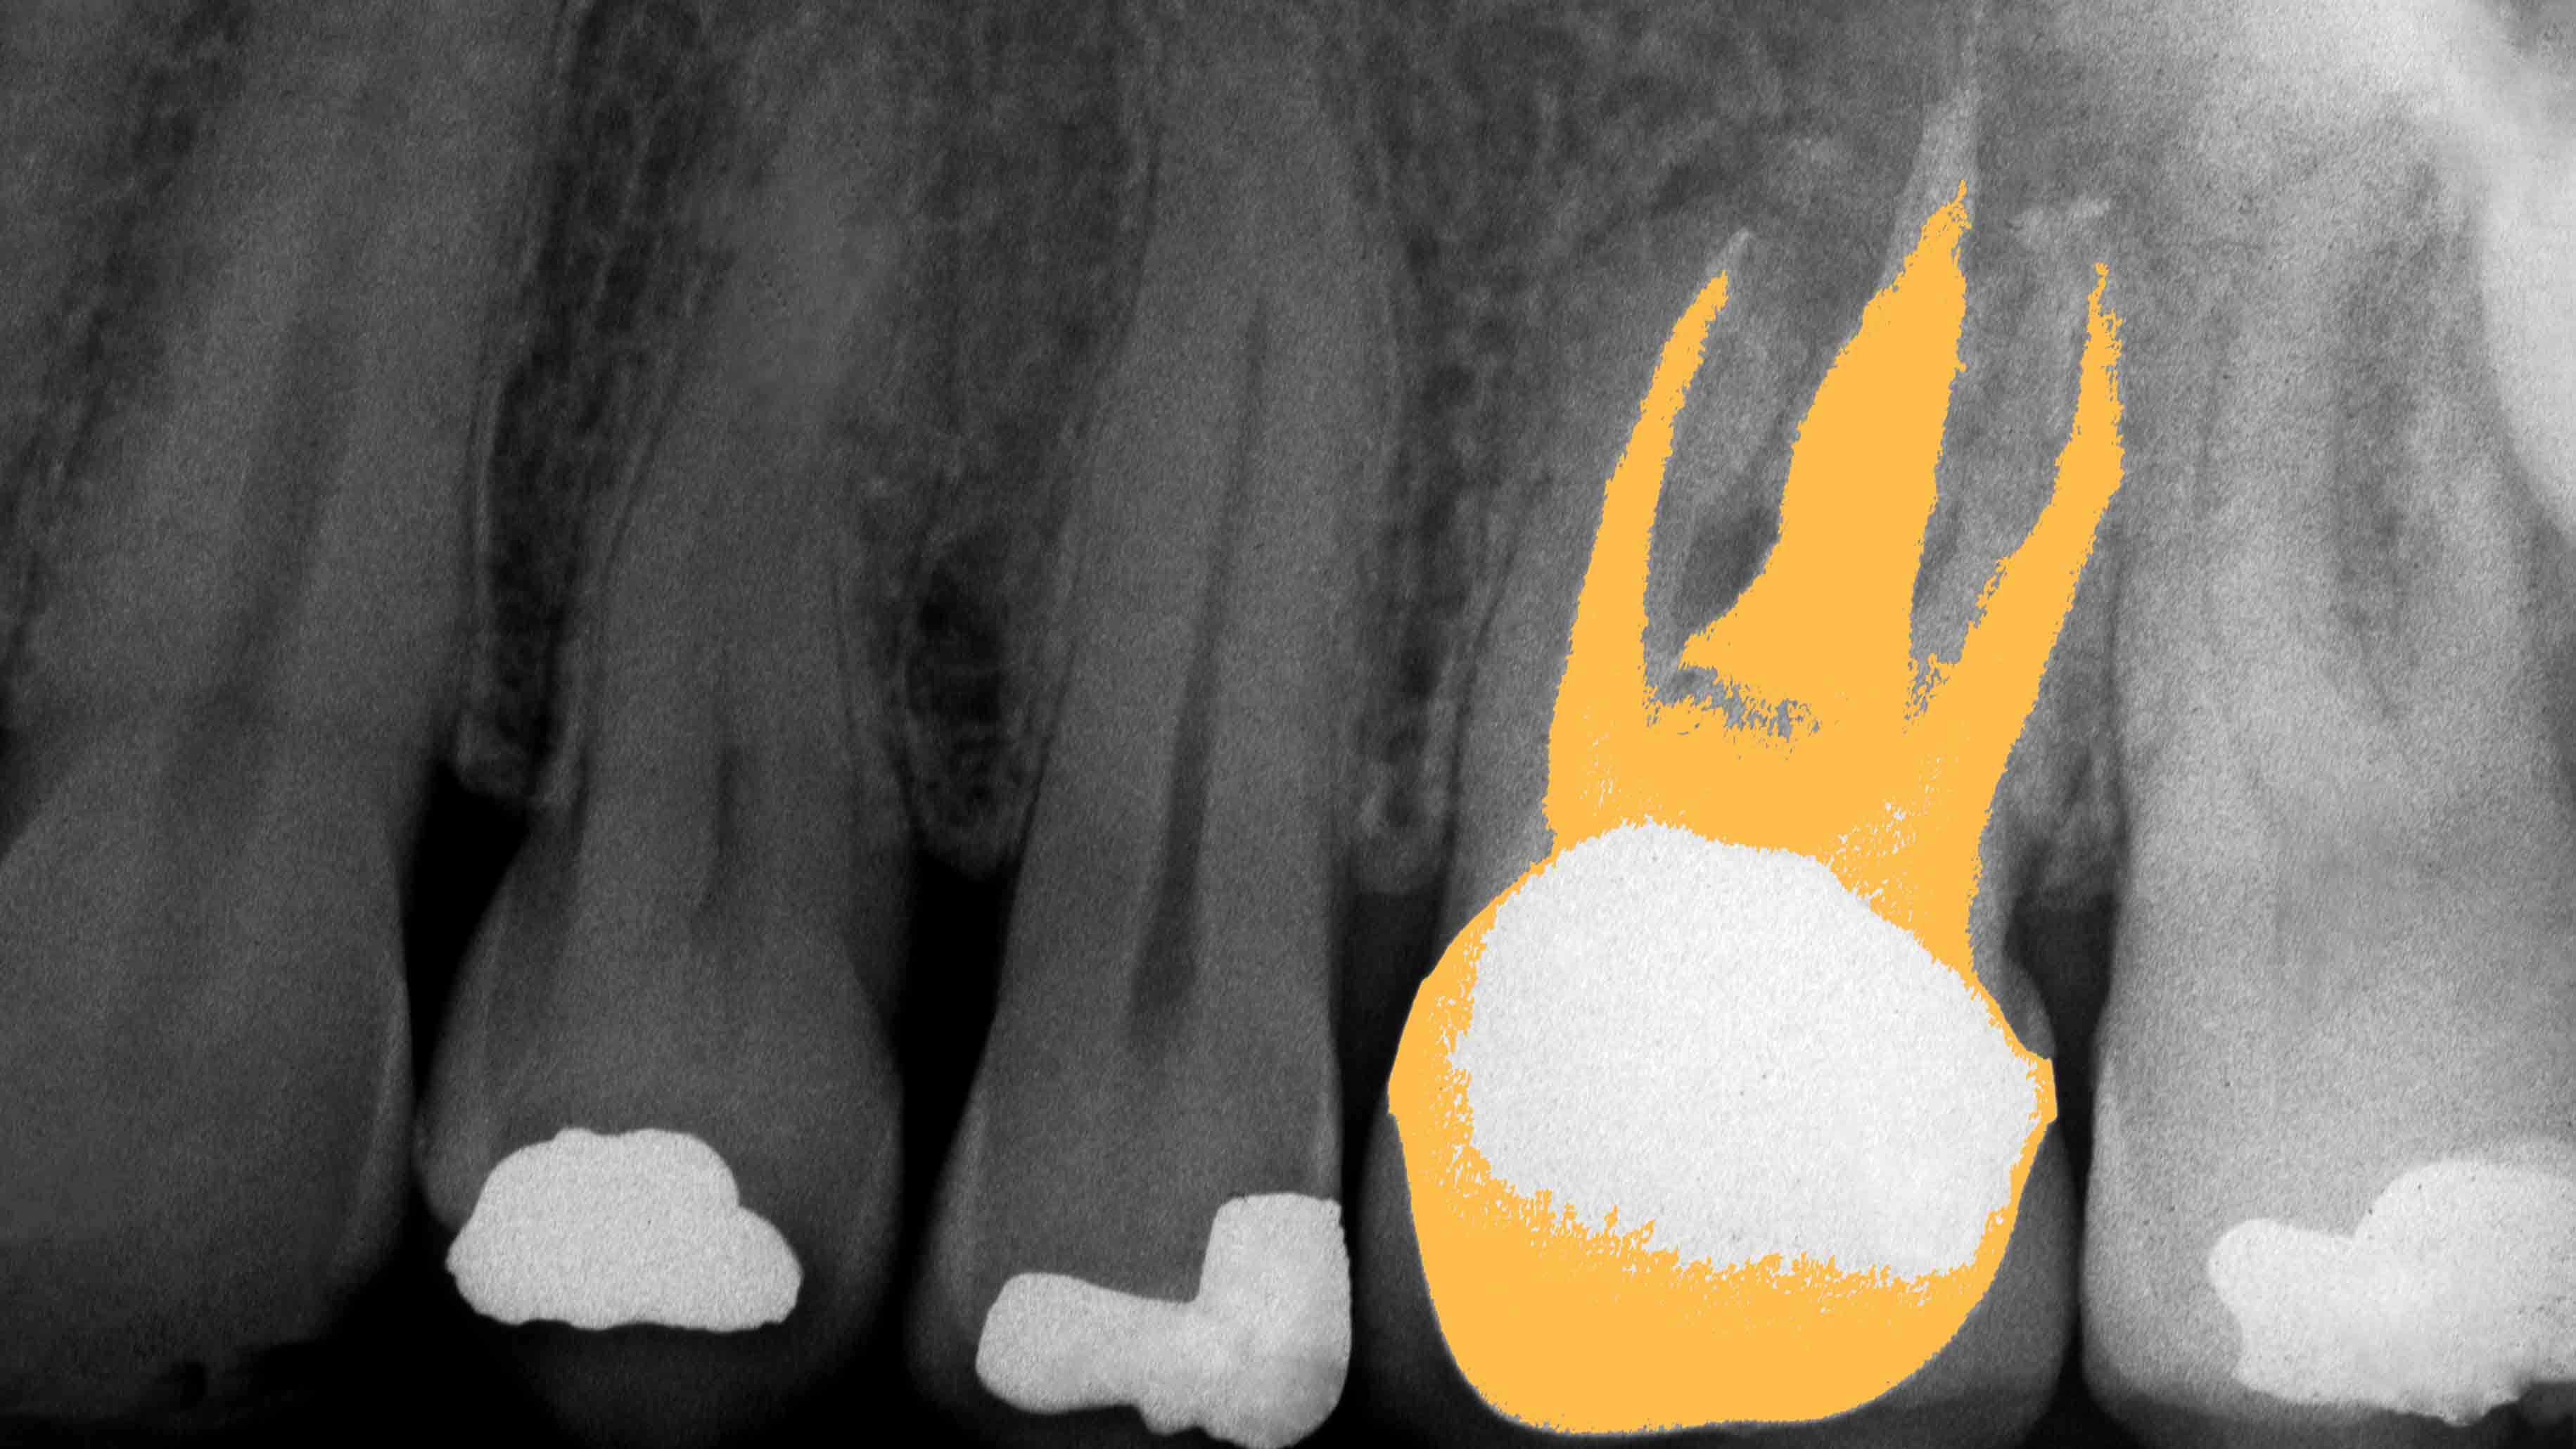

The study, carried out in China on 40 children who had both damaged adult teeth and baby teeth that had yet to fall out, was published in the journal Science Translational Medicine.The test subjects were selected to either receive the new treatment or an older treatment called apexification, which attempts to address the issue by encouraging root development. This was considered the control group.

The patients who received the stem cell treatment, called human deciduous pulp stem cell (hDPSC) treatment, had pulp tissue taken out of one of their healthy baby teeth. This pulp is rich in stem cells. The cells were grown in a lab and then placed into the injured adult tooth. The hope was that the stem cells would encourage the growth of new pulp inside the tooth.

Follow-ups were carried out for up to three years. The patients who had received the hDPSC treatment showed better blood flow in their teeth, better root systems, and thicker dentin than the patents who underwent the traditional procedure. They also had recovered sensation in their teeth, while the control group had not. The use of a patient’s own cells in the treatment also reduced the risk of their body rejecting the therapy, making the concept even more attractive.